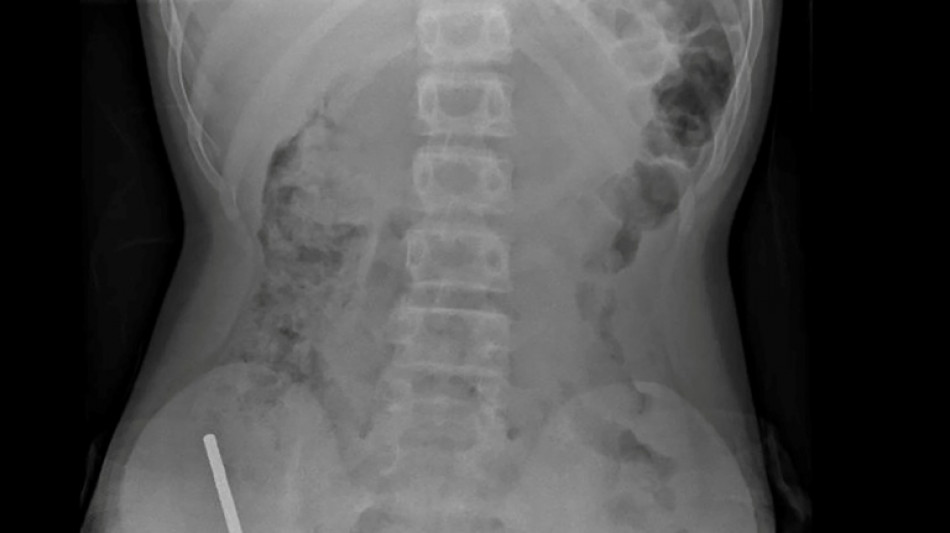

An X-ray showed the magnets had clumped together in four straight lines inside the child's intestines.

"These appeared to be in separate parts of bowel adhered together due to magnetic forces," they said.